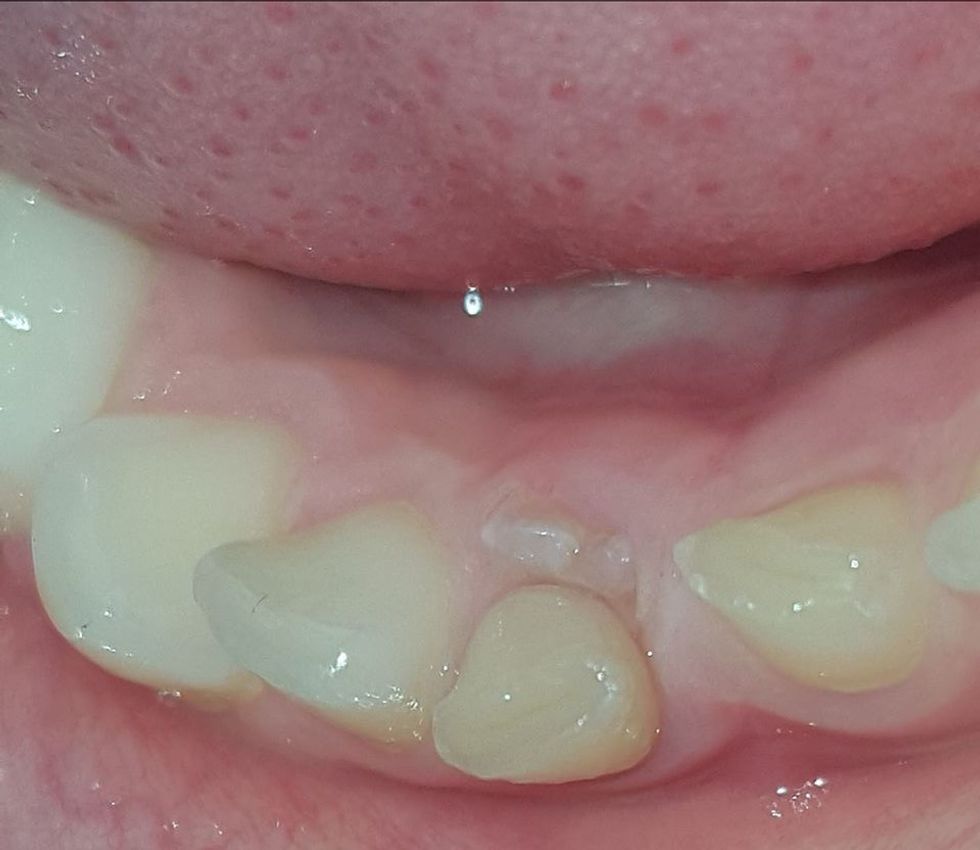

Shih foton sipër si duken dhëmbët ku janë shkrirë rrënjët dhe njëri prej tyre ku rrënja nuk është shkrirë.

Në përgjithësi te dhëmbët e qumështit me kalimin e kohës rrënjët shkrihen (rezorbohen) dhe në momentin që këta dhëmbë fillojnë të lëvizin, mbetet vetëm kurora, gjë e cila e lehtëson procedurën e nxjerrjes së këtyre dhëmbëve. Kjo procedurë mund të kryhet vetëm me sprej anestezion.

Në raste më të rralla, tek disa dhëmbë të qumështit nuk shkrihet rrënja dhe procedura e nxjerrjes së tyre mund të vështërsohet dhe mund të sjellë ndjeshmëri e dhimbje tek fëmijët dhe ky është momenti kur shumë fëmijë marrin trauma dhe humbin besimin tek dentisti.